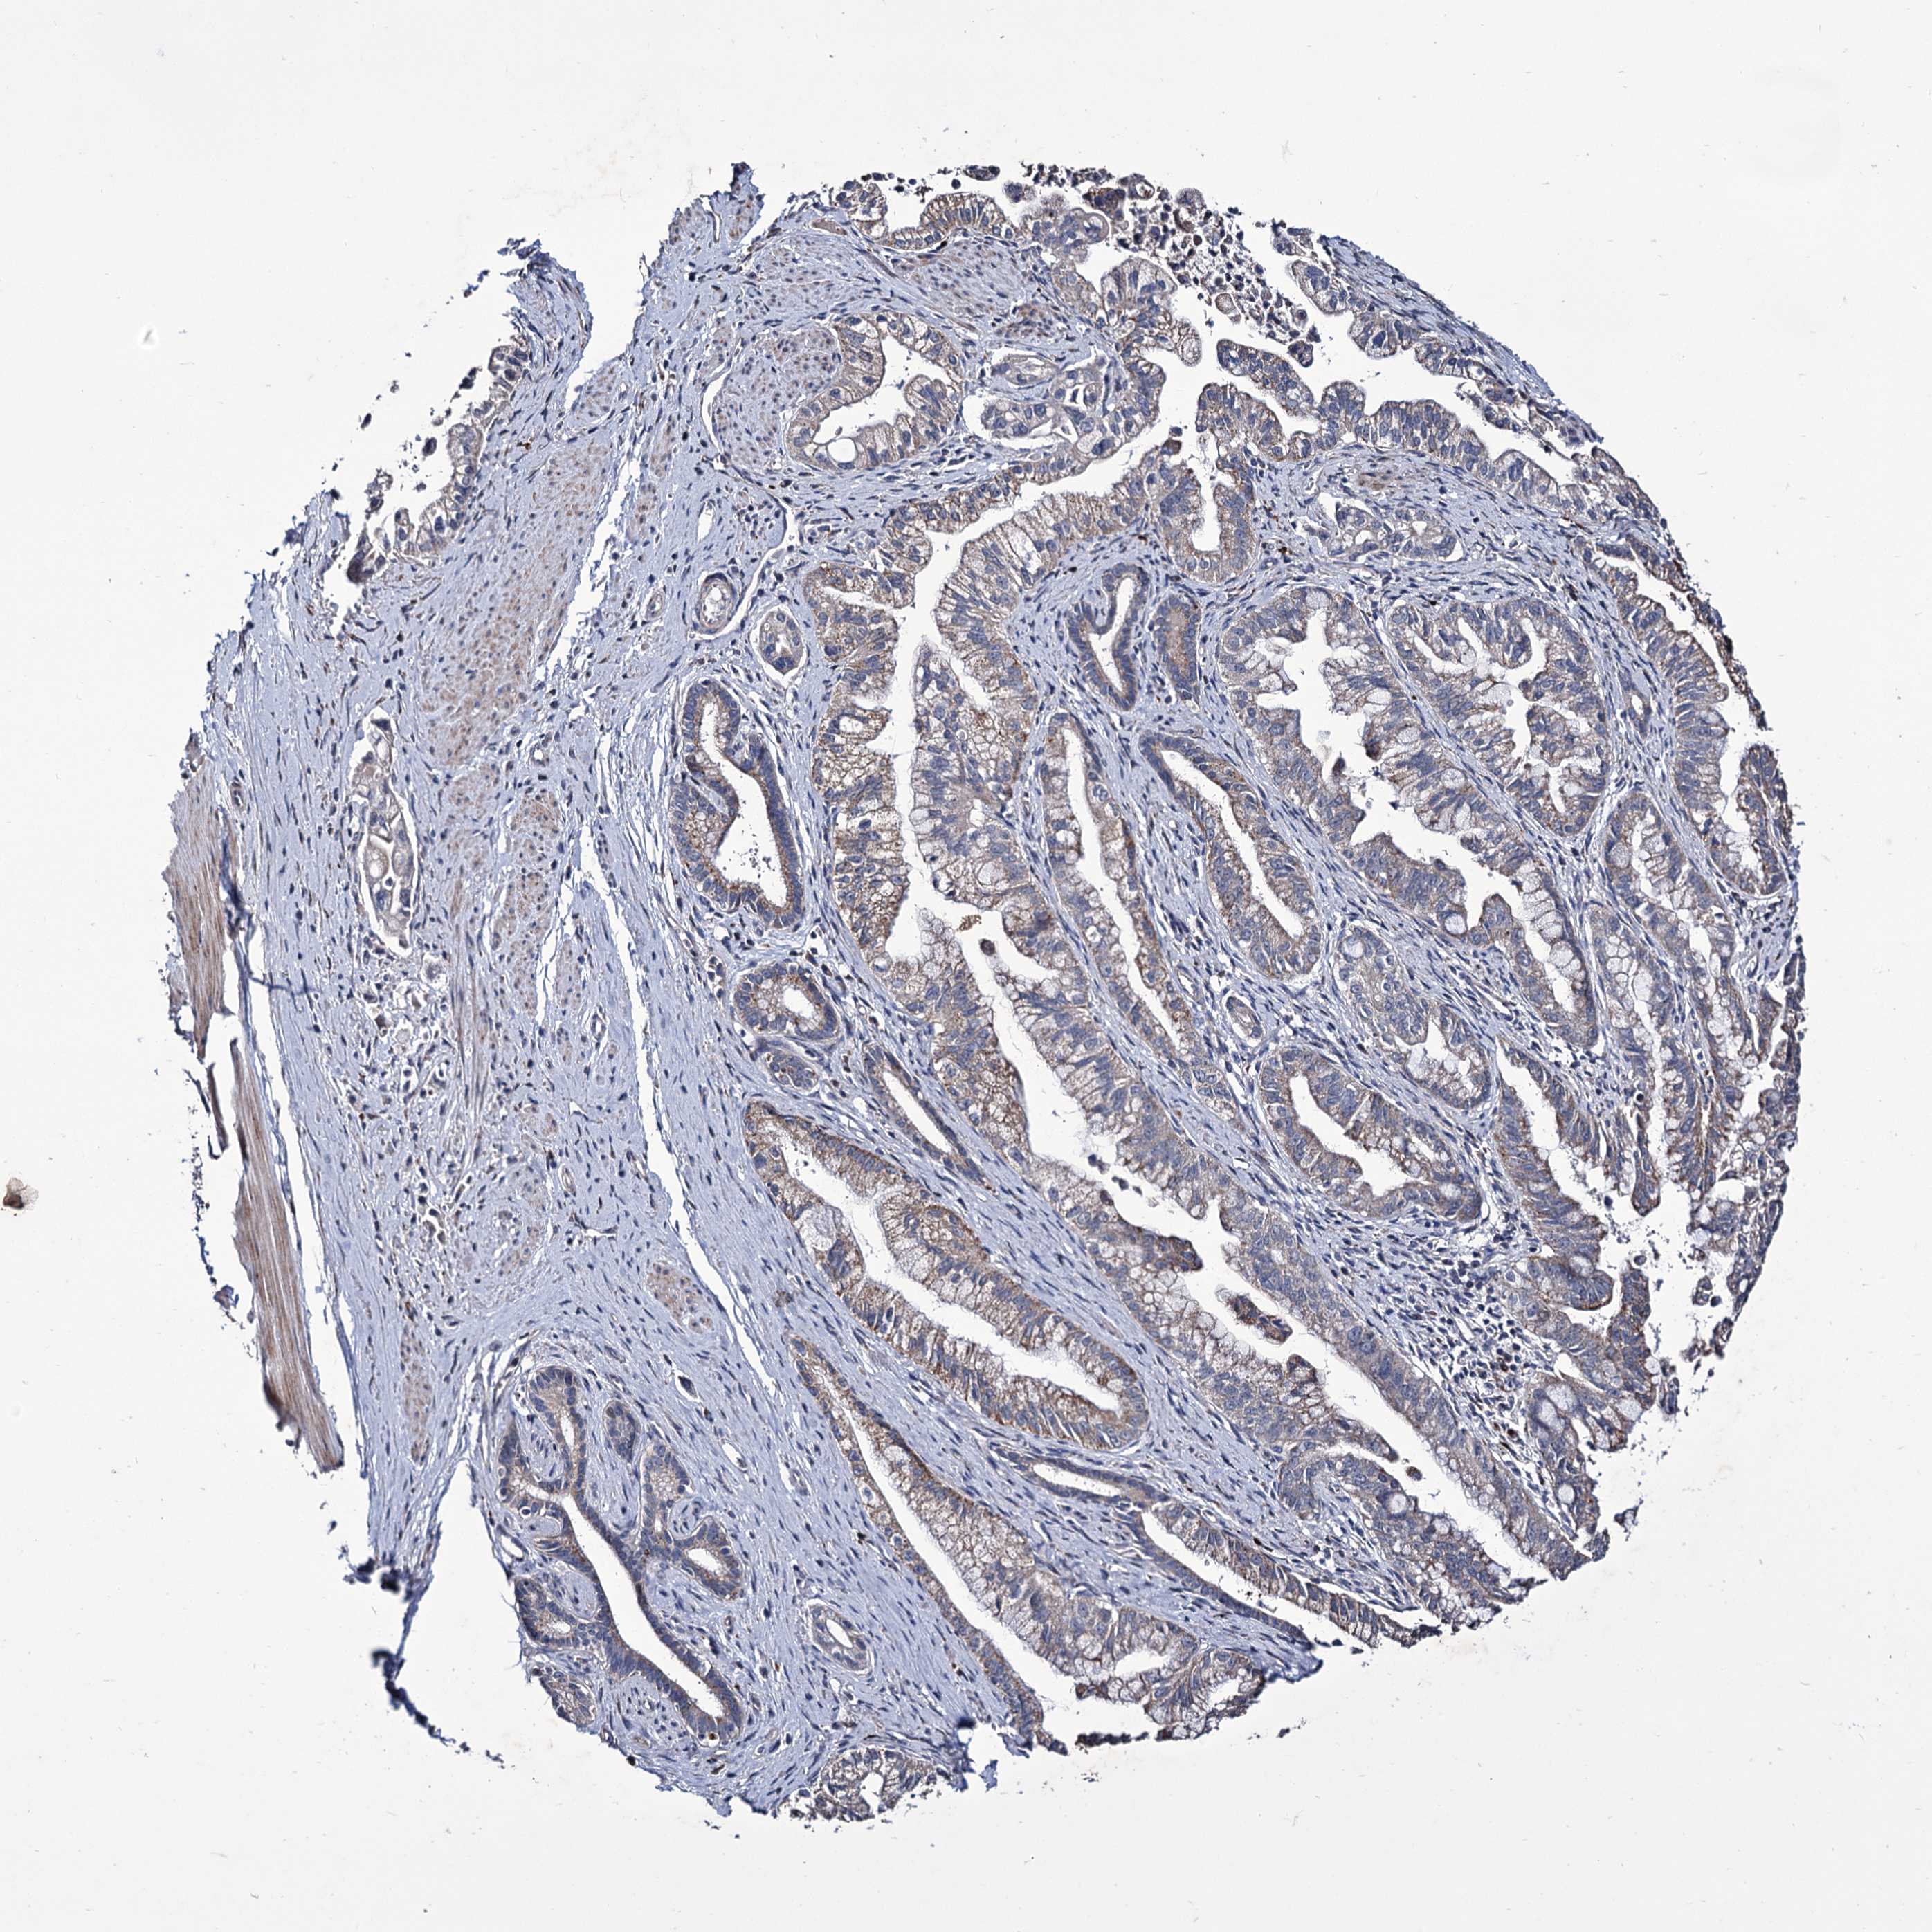

PANCREATIC CANCER - Protein expressioni

A mouse-over function shows sample information and annotation data. Click on an image to view it in a full screen mode. Samples can be filtered based on level of antibody staining by selecting one or several of the following categories: high, medium, low and not detected. The assay and annotation is described here.

Note that samples used for immunohistochemistry by the Human Protein Atlas do not correspond to samples in the TCGA dataset.

Antibody stainingi

Antibody staining in the annotated cell types in the current human tissue is reported as not detected, low, medium, or high, based on conventional immunohistochemistry profiling in selected tissues. This score is based on the combination of the staining intensity and fraction of stained cells.

Each image is clickable and will lead to virtual microscopy that enables deeper exploration of all samples and also displays staining intensity scores, fraction scores and subcellular localization as well as patient and tissue information for each sample.

Antibody HPA039366

Staining

High

Medium

Low

Not detected

Intensity

Strong

Moderate

Weak

Negative

Quantity

>75%

75%-25%

<25%

None

Location

Nuclear

Cytoplasmic/membranous

Cytoplasmic/membranous,nuclear

Adenocarcinoma, NOS